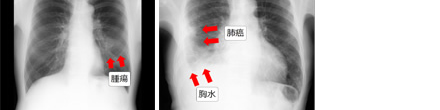

胸部X線検査は、X線検査の中で最も簡単な検査方法ですが、肺や心臓、肺の間にある縦隔などの器官の病気について、様々な情報を得ることができます。

肺がんや肺結核、肺炎などでは、異常が白い影として映ります。気胸、肺気腫などは病気のあるところの空気が多くなるので、黒く映ります。気管支拡張症や胸水の有無なども分かります。